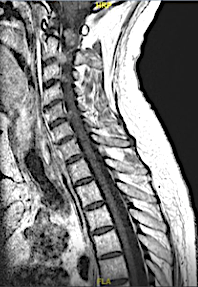

Paciente con clínica de mielopatía cervical de años de evolución, enmascarada por una PNP severa que era tratada con inmunoterapia (cuando ésta no fue efectiva, se realizó RM).

RM postoperatoria: sólo se extirparon los schwannomas C2 que causaban clínica compresiva